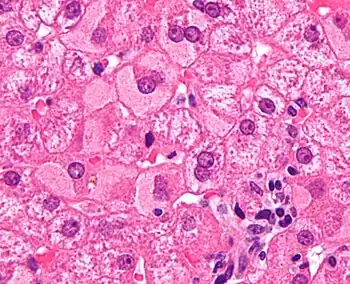

Ground glass hepatocytes